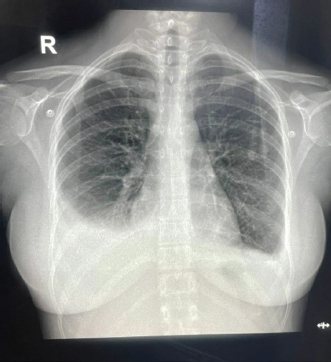

USG’s whole abdomen revealed hepatomegaly and mild to moderate ascites. In view of melena and thrombocytopenia, 6 units of random donor platelets were transfused. A workup for fever with thrombocytopenia and polyserositis was started. Dengue RTPCR, NS1 antigen, IgM, Weil felix, and VDRL were negative. Viral markers (HIV/HBsAg/Anti HCV/Anti HAV IgM/Anti HEV IgM) were negative. Scrub IgM, Brucella IgM, Urinary legionella antigen, CMV PCR, and Leptospira IgM were negative. Malaria Ag and P/S for the malaria parasite were negative. The widal test and Typhidot IgM were negative. CPK and CK-MB were negative. Stool occult blood (three samples) were negative. Covid PCR was negative. Blood and urine C/S were negative. Urine KOH revealed few budding yeast cells. Urine fungal culture was negative. Workup for EBV revealed 24,300 copies of EBV RTPCR and EBV IgM and IgG were positive. We did an autoimmune workup considering a young female with polyserositis but both ANA by Immunofluorescence and ANA profile were negative. Direct and indirect Coombs tests were negative. By the end of first week of admission, thrombocytopenia started improving but she had a persistent cough and fever although spikes were reduced. A 2D echo revealed trace pericardial effusion. Repeat Chest X-ray revealed persistent bilateral pleural effusion (Right > Left) (Fig. 2). In view of persistent effusion, we decided to perform a CECT chest and abdomen which revealed evidence of moderate right pleural effusion, minimal fluid in the left pleural cavity with atelectatic changes in the adjacent lung, oedematous thickened gallbladder and mild ascites (Figs. 3 and 4).

Fig. 3. CECT chest suggestive of bilateral pleural effusion Right > left, minimal pericardial effusion.